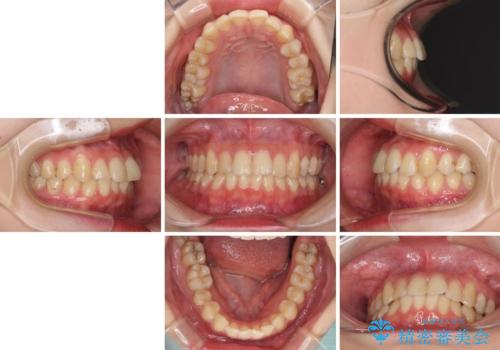

- 上下前歯のデコボコを気にして来院された患者様です。

以前矯正をした後戻りということで、歯列不正はそれほど大きくなかったため、インビザライン・ライトを用いて矯正治療を行うこととしました。

インビザラインは1日に22時間を目安に装着していただきますが、装着時間が十分でないとシミュレーション通りに動かないことがあります。

前歯のデコボコが残っており、シミュレーション通りに動いていない部分がありましたが、再矯正であることやご本人の満足いくところまでデコボコが改善されたとのことで、治療を終了することとしました。